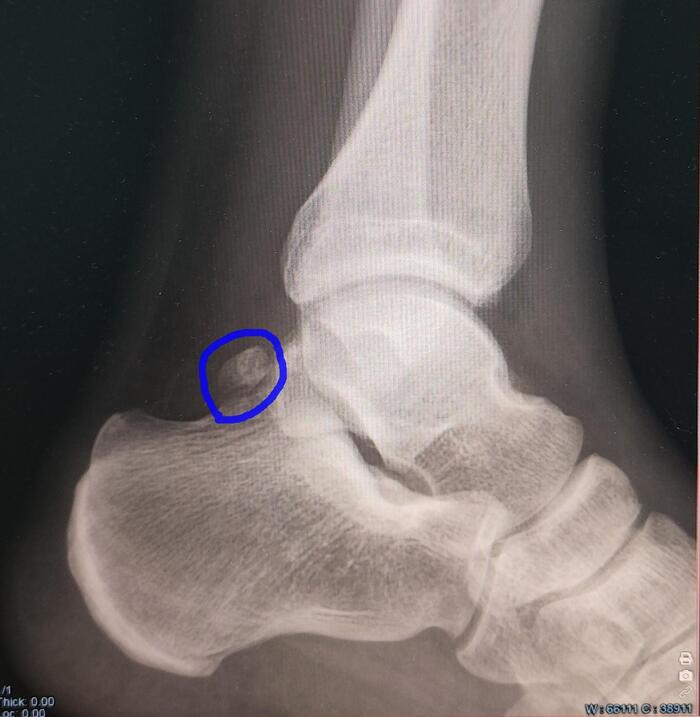

Описание: на Р-граммах левого гс/с в 2х проекциях суставная щель не сужена, субхондральный склероз, краевые остеофиты-не выявлены. По заднему контуру таранной кости определяется наличие дополнительной кости-os trigonum. Заключение:Os trigonum(аномалия развития левой стопы), наиболее вероятно вызывающая синдром компрессии таранной кости.

Категория годности с диагнозом Os trigonum(аномалия развития левой стопы), наиболее вероятно вызывающая синдром компрессии таранной кости-по статье 69г Б3-годен к военной службе с незначительными ограничениями.